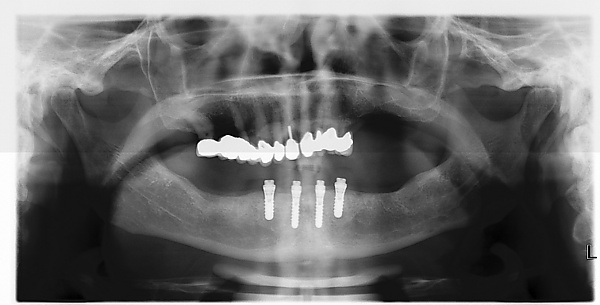

- имплантация All-on-4 («все на 4») — это зубопротезирование полного зубного ряда методом имплантации четырех искусственных корней (имплантатов) в костную ткань челюсти пациента с последующей установкой на них протеза.[1]

- с помощью рентгенографии изучаются качество и плотность костной ткани;